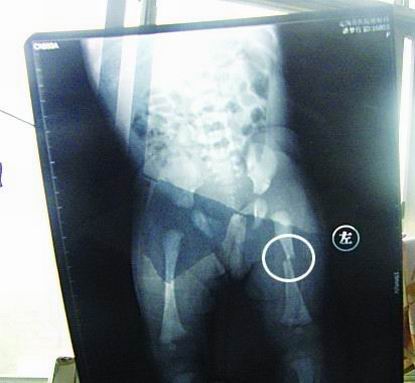

CT顯示小夢(mèng)竹左下肢骨折

今年7月2日下午,定陶縣南王店鄉(xiāng)沈莊村孕婦聶元真,在定陶縣人民醫(yī)院剖腹產(chǎn)下一女?huà),取名為潘?mèng)竹。醫(yī)院說(shuō),嬰兒出生后窒息,診斷為新生兒缺血缺氧性腦病,頭皮血腫。當(dāng)晚發(fā)現(xiàn)女?huà)胱笙轮课划惓,第二天拍片顯示為左下肢骨干骨折。7月3日,潘夢(mèng)竹的頭顱CT顯示其頭頂部骨折,蛛網(wǎng)膜下腔出血,顱內(nèi)血腫。